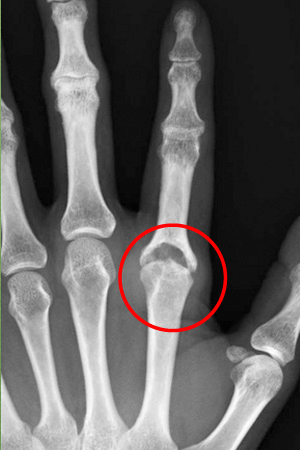

症例1

135歳女性の患者さん、人差し指の第3関節(MP関節)に炎症を起こし腫れていました。

2ステロイド関節内注射により腫れは引きましたが、痛みが持続するためMRIを撮ってみると、滑膜の炎症が残っていました。

3そのため手術をして滑膜除去を行ったところ、スッキリしネイルアートも楽しめるようになりました。